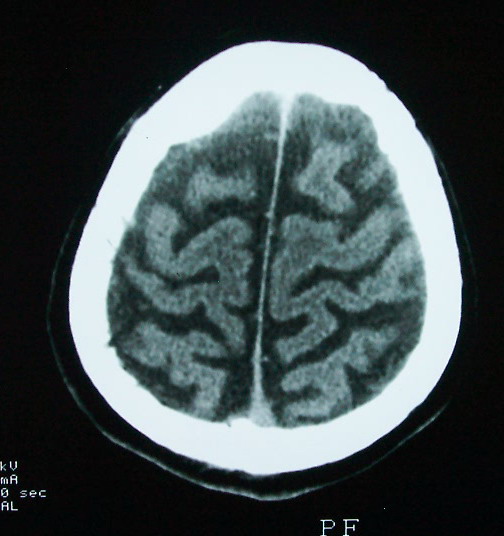

以下是引用余辉在2009-4-15 20:49:00的发言:[br]右侧病灶发生于冠状缝区,但额骨左侧鳞也有病灶,病灶区脑沟裂增宽(有脑萎缩征像,把这个征像放在颅骨病变一起考虑可能有点牵强),是否可能是板障血管畸形所致谢?抑或是嗜酸性肉芽肿或蛛网膜粒压迹那类东西?

以下是引用whzht在2009-4-15 20:57:00的发言:[br]1、额骨改变,考虑蛛网膜粒压迹;[br]2、脑萎缩。